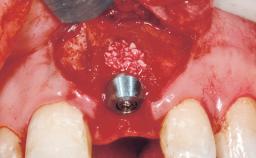

Placement Protocol Immediate implant placement

Socket Morphology Single-root socket

Socket Integrity Damage to one or more bone walls

Bone Volume Damage to one or more socket walls